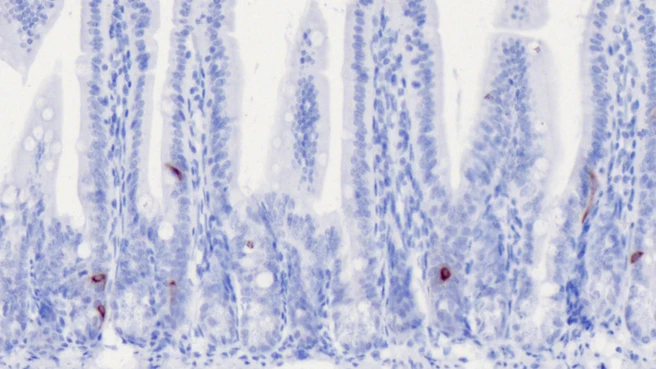

Dr. Eva Rath's team used biopsies to examine the intestine itself – specifically its epithelial cells, which form the intestinal barrier. This cellular layer also contains enteroendocrine cells. The results were clear: mice with intestinal inflammation and humans with Crohn's disease had fewer cells that produced GLP-1. In addition, transcription analyses showed that this decline begins even before the inflammation becomes noticeable.